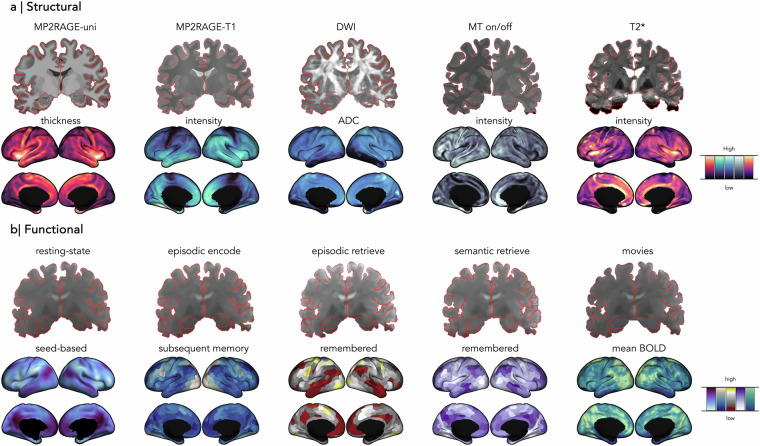

多模态神经成像,特别是磁共振成像(MRI),可以跨多个尺度对人脑结构和功能进行无创检查。精确的神经成像建立在这个基础之上,能够在单个个体中以高保真度绘制大脑结构、功能和连接模式。高场MRI在7特斯拉(T)或更高的磁场强度下工作,提高了信噪比,并为获得空间分辨率开辟了可能性。在这里,我们共享了一个多模态精确神经成像和连接组学(PNI) 7 T MRI数据集。10名健康个体接受了全面的MRI方案,包括T1松弛测量,磁化转移成像,T2*加权成像,弥散MRI和多状态功能MRI范式,在三个成像过程中汇总。除了匿名的原始MRI数据外,我们还从不同的方式跨多个分割尺度发布了皮质范围内的连接体,并提供了“梯度”,以紧凑地表征皮层组织的空间模式。我们的精确MRI数据集将促进我们对个体人脑结构-功能关系的理解,并通过开放科学框架公开提供。

Multimodal neuroimaging, in particular magnetic resonance imaging (MRI), allows for non-invasive examination of human brain structure and function across multiple scales. Precision neuroimaging builds upon this foundation, enabling the mapping of brain structure, function, and connectivity patterns with high fidelity in single individuals. Highfield MRI, operating at magnetic field strengths of 7 Tesla (T) or higher, increases signal-to-noise ratio and opens up possibilities for gains spatial resolution. Here, we share a multimodal Precision Neuroimaging and Connectomics (PNI) 7 T MRI dataset. Ten healthy individuals underwent a comprehensive MRI protocol, including T1 relaxometry, magnetization transfer imaging, T2*-weighted imaging, diffusion MRI, and multi-state functional MRI paradigms, aggregated across three imaging sessions. Alongside anonymized raw MRI data, we release cortex-wide connectomes from different modalities across multiple parcellation scales, and supply "gradients" that compactly characterize spatial patterning of cortical organization. Our precision MRI dataset will advance our understanding of structure-function relationships in the individual human brain and is publicly available via the Open Science Framework.